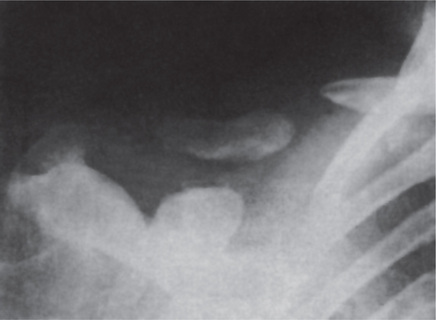

Fibrous dysplasia of the maxilla is an especially serious form of the disease since it has a marked predilection for occurrence in children and is almost impossible to eradicate without radical, mutilating surgery (Fig. 17-8). These lesions are not well circumscribed, commonly extend locally to involve the maxillary sinus, the zygomatic process and the floor of the orbit, and even extend back toward the base of the skull. Severe malocclusion and bulging of the canine fossa or extreme prominence of the zygomatic process, producing a marked facial deformity, are typical sequelae of this disease in this location need not be truly monostotic, but neither is it usually classified as a polyostotic type. It has sometimes been referred to as craniofacial fibrous dysplasia, since it does affect the craniofacial complex and is so characteristic in its clinical and radiographic features that it closely resembles a distinct entity (Fig. 17-9). This form of the disease has been described in detail by Waldron and Giansanti and by Eversole and his associates.